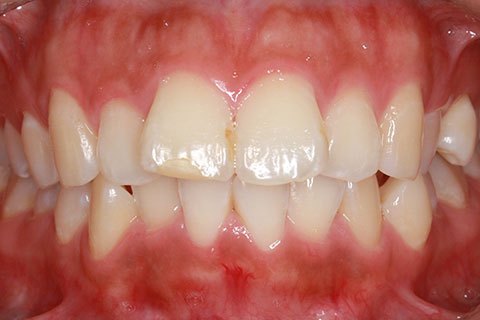

治療後

- 年齢・性別

- 25歳女性

- 治療期間

- 2年0ヶ月

- 抜歯

- 上下4番抜歯

- 治療費

- 110万円

- 表側矯正と比較して、力学的な操作性が複雑なため、ボーイングエフェクトを起こしやすい。